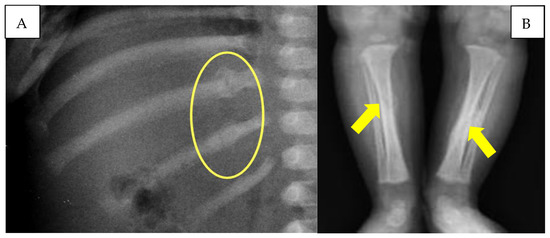

The infant also underwent a chest X-ray, which showed the presence of multiple rib fractures and a left clavicular fracture. The lower limb X-ray documented the presence of a tibial diaphyseal spiral fracture bilaterally undergoing ossification, with the presence of bony callus more significant on the left tibia (Figure 4).

Figure 4.

(A) Rib fractures with reparative phenomena (yellow circle). (B) Diaphyseal tibial spiral fractures (yellow arrows).

On the other hand, with regard to the spiral fractures of the tibiae and the multiple costal fractures, the presence of bone callus on radiographic images made it possible to define the lesions as non-coincident with cranio-encephalic trauma. In particular, the tibial fractures, due to the particular spiral conformation, were not correlated with direct traumatism but due to a mechanism of extreme rotation of each lower limb. The detected rib fractures, located at the level of the posterior arch of two adjacent ribs, are also typically frequent in cases of child abuse [38]. For all these reasons, the authors identify the pathogenetic mechanism on the basis of the head injury observed in the child as a case of ‘Compressed Baby Head’ (Figure 7).